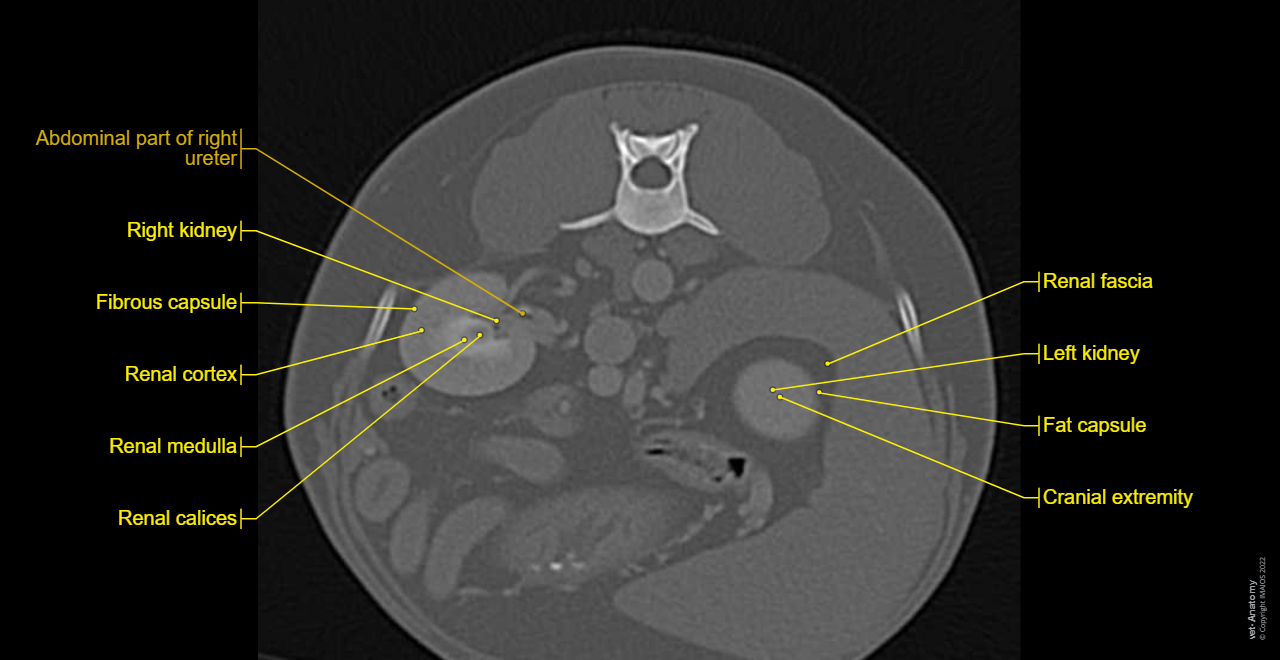

Dog - Urinary organs: Kidney, Ureter, Urinary bladder, Male urethra

Kidney - Dog - Anatomy atlas

Kidney